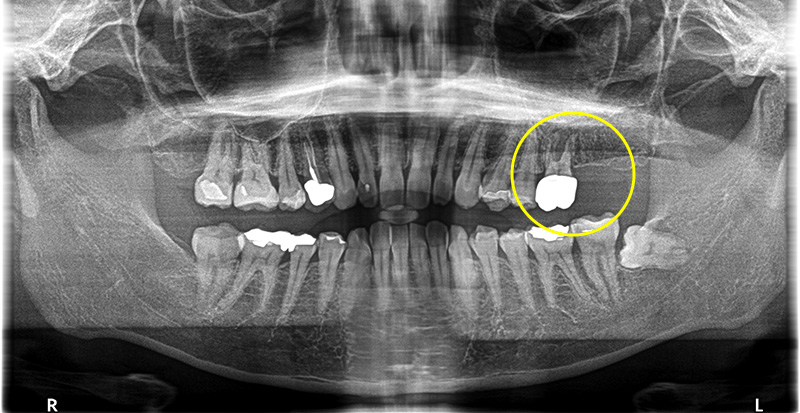

上部構造(人工歯)の装着・治療完了

本来大臼歯は2本ある為、この患者さまの場合2本インプラントを入れることが理想的だが、今回は金額をなるべく抑えたいとのことで、6番の歯のみインプラントを埋入し、短縮歯列にしています。

術後は奥歯で硬いものもしっかりと噛むことができるようになり、大変満足していただいています。

今後、コストの目途がたったら7番目のインプラントも埋入する予定です。